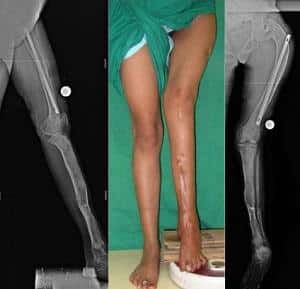

Большая берцовая кость

Фиброзная дисплазия большеберцовой кости приводит к укорочению одной ноги по сравнению с другой, что в свою очередь вызывает нарушения в походке и осанке, хромоту и затруднения в нормальной работе опорно-двигательного аппарата.

Лечение этого состояния осуществляется через хирургическое вмешательство, направленное на пластику пораженных суставов и установку трансплантата.

После операции начинается восстановительный период, в течение которого пациент находится под внимательным наблюдением врачей. В этот период передвижение осуществляется с помощью костылей до полного заживления и восстановления области большеберцовой кости.